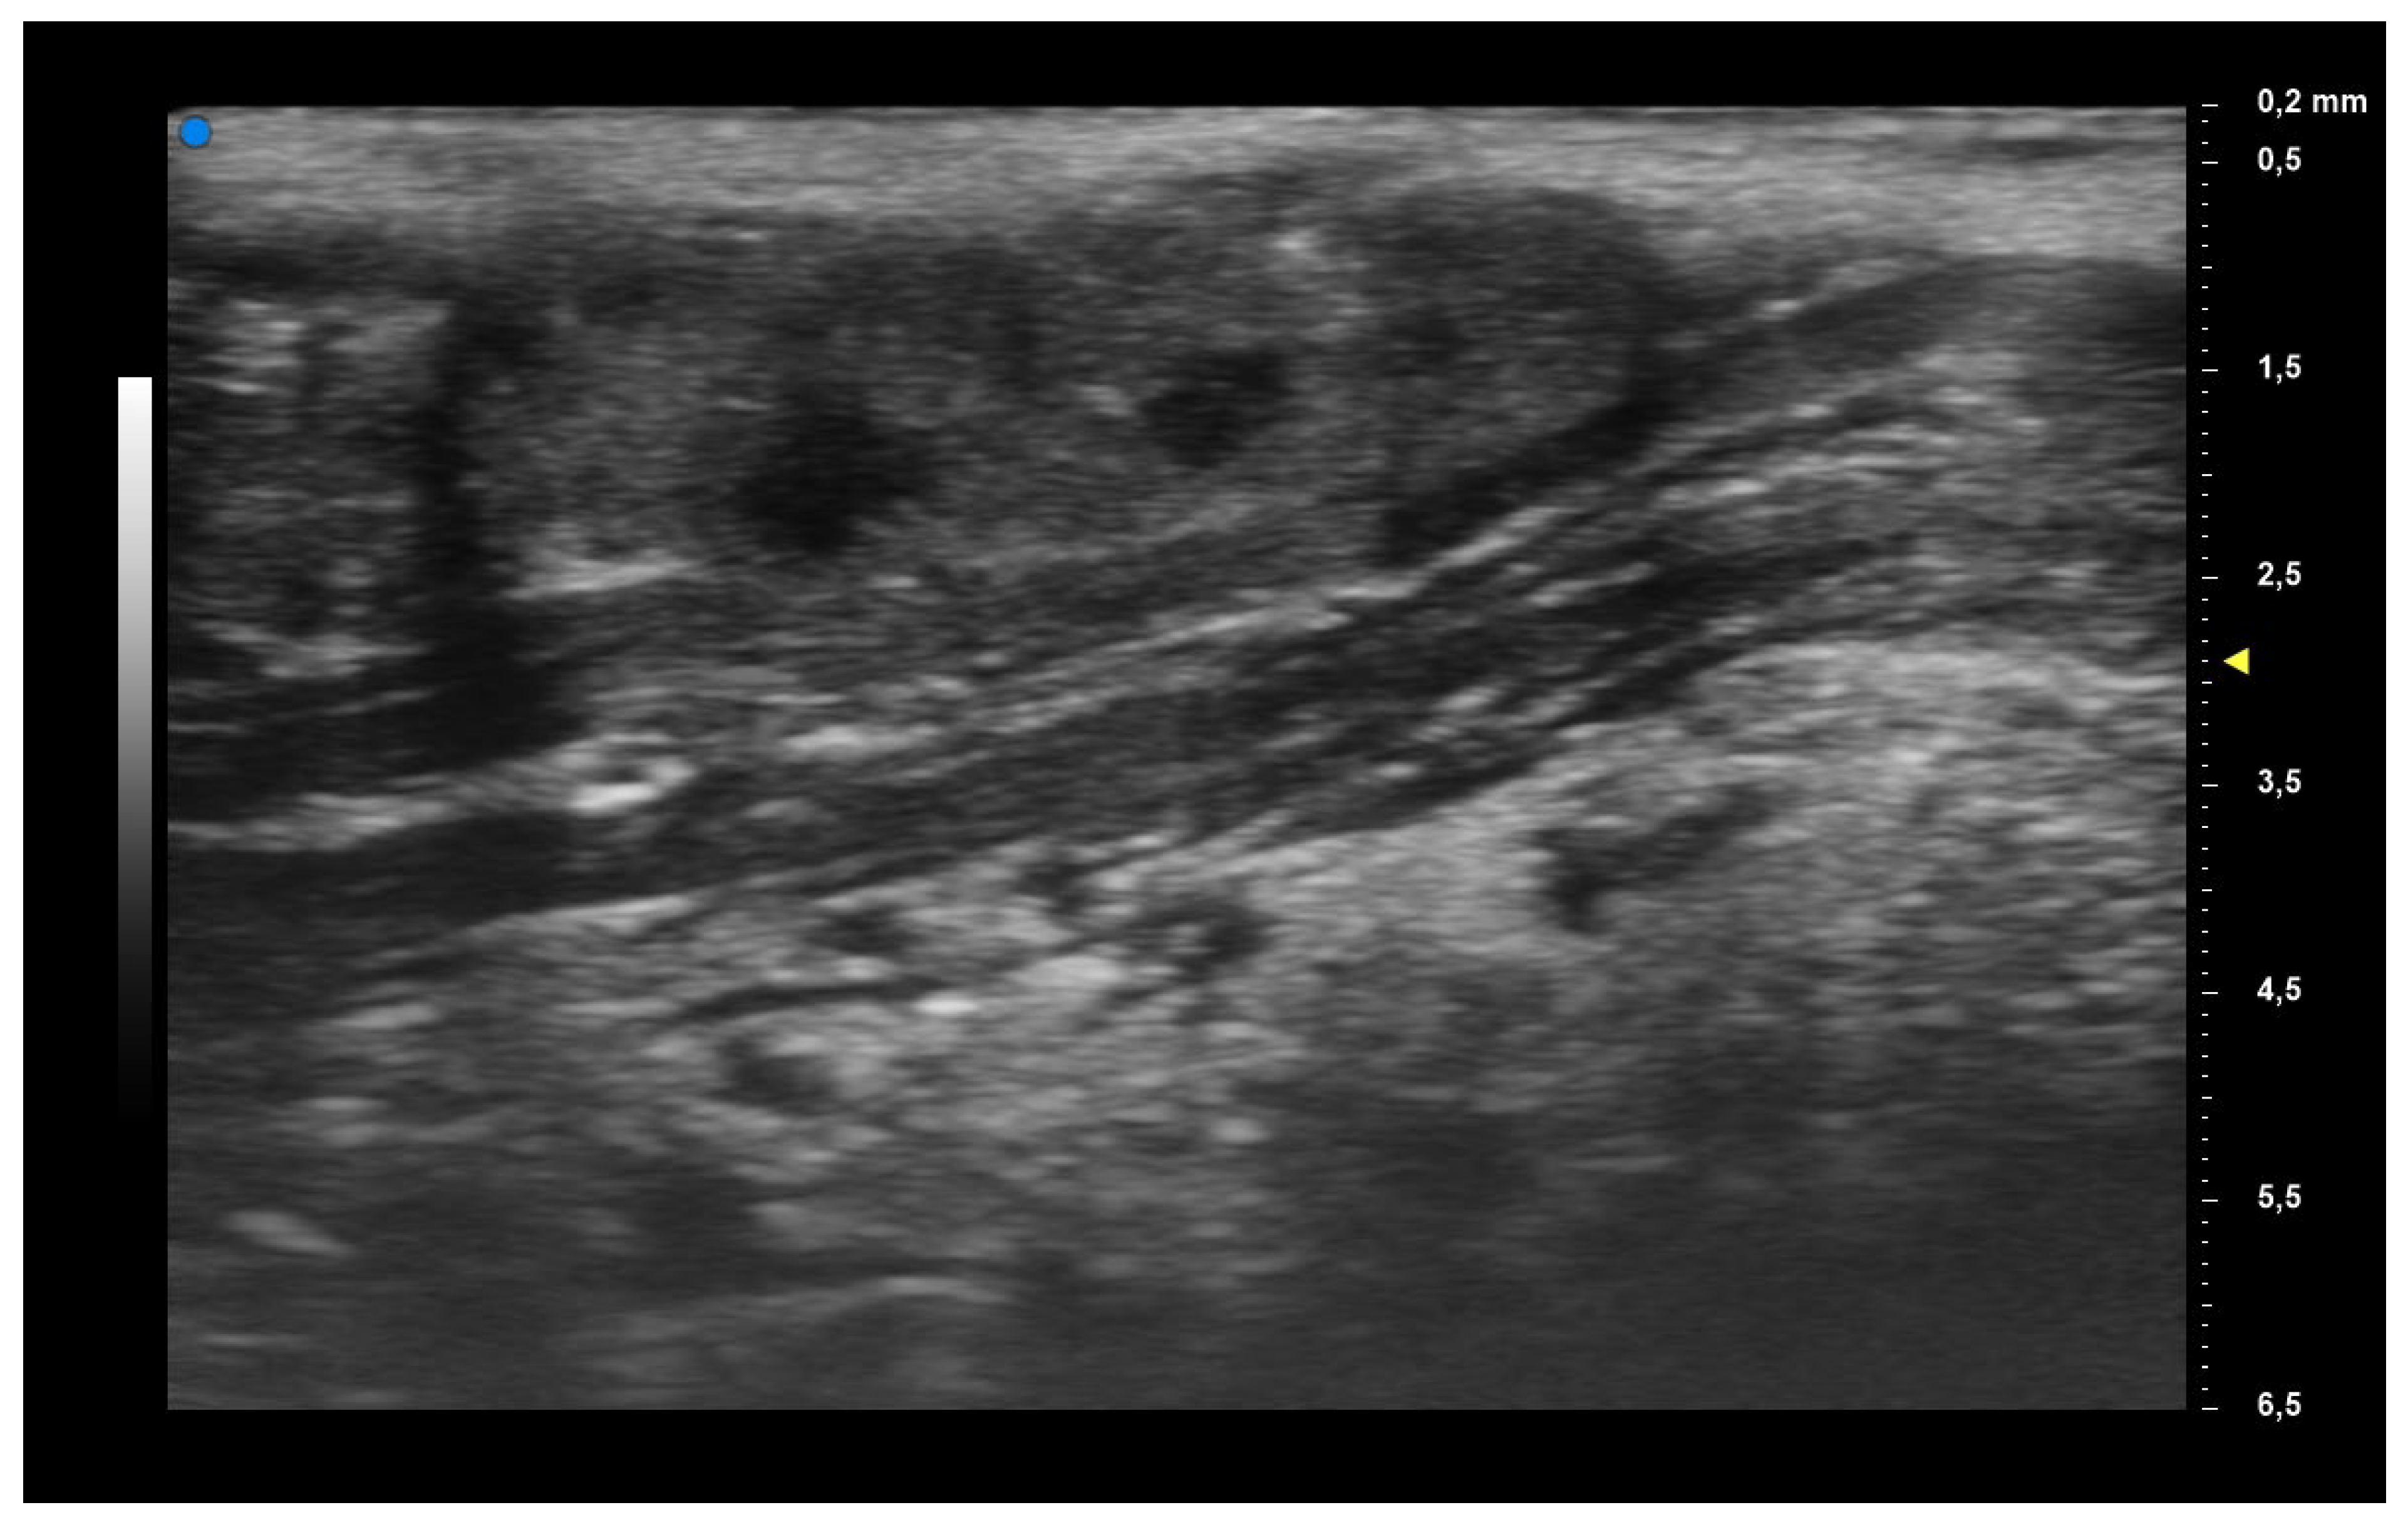

| UHFUS Characteristics | Sicca Syndrome (n = 4) | Parotitis (n = 2) | Non-Sicca, Non- Parotitis (n = 6) | Total (n = 12) |

|---|---|---|---|---|

| Grade 1 | 3 (75%) | 1 (50%) | 4 (67%) | 8 (67%) |

| Grade 2 | 0 (0%) | 1 (50%) | 1 (17%) | 2 (17%) |

| Grade 3 | 1 (25%) | 0 (0%) | 1 (17%) | 2 (17%) |

| Mild vascularization | 1 (25%) | 1 (50%) | 1 (17%) | 3 (25%) |

| Moderate vascularization | 3 (75%) | 1 (50%) | 5 (83%) | 9 (75%) |